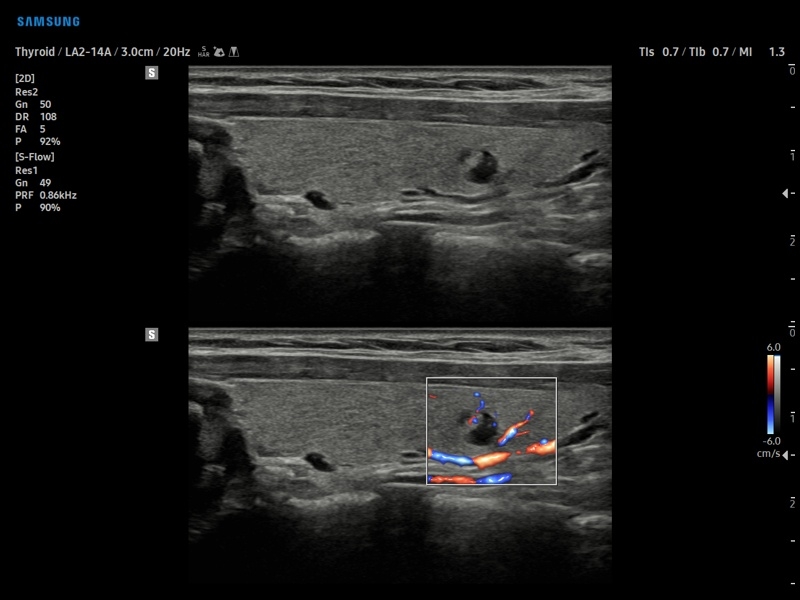

• МодульS-Detect Breast- программа автоматического обнаружения и анализа образований молочной железы у женщин, измерение и классификация по системе BI-RADS.

• МодульS-Detect Thyroid- программа автоматического обнаружения образований и анализа щитовидной железы, измерение и классификация по системе системе TI-RADS.

• Модуль S-Detect Thyroid - программа автоматического обнаружения образований и анализа щитовидной железы, измерение и классификация по системе системе TI-RADS.